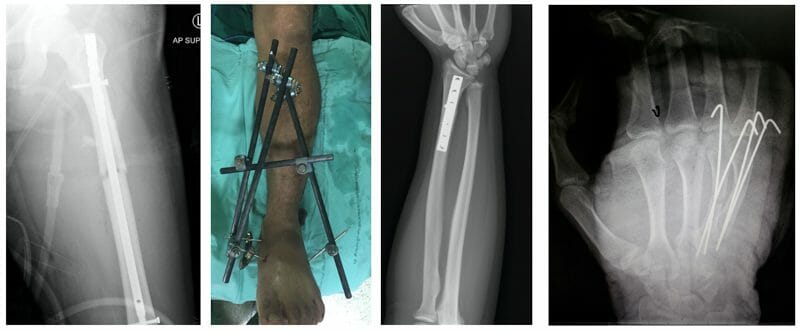

อุปกรณ์สำหรับรักษากระดูกหัก (Implants options for fracture)

- เหล็กแกนสอดในโพรงกระดูก (intramedullary nail) การใช้เหล็กแกนในการยึดตรึง กระดูกนั้น ใช้เทคนิคในการผ่าตัดเปิดแปลขนาดเล็กได้ โดยผ่าตัดเปิดแผลที่บริเวณปลายกระดูก จากนั้นจึงสอดเหล็กแกนเข้าไปในโพรงกระดูก โดยไม่จำเป็นต้องกระทบกระเทือนกับตำแหน่งที่ได้รับบาดเจ็บ อย่างไรก็ตามการผ่าตัดด้วยวิธีนี้ไม่สามารถใช้ได้กับกระดูกหักทุกส่วน

- เหล็กยึดตรึงกระดูกจากภายนอก (external fixation) มักใช้กับผู้ป่วยที่มีกระดูกหักแบบแผลเปิด มีสิ่งสกปรกในแผล

- เหล็กแผ่นและสกรูยึดตรึงกระดูก (plate and screws) แต่เดิมจำเป็นต้องเปิดแผลยาวและเลาะกล้ามเนื้อมาก เพื่อยึดตรึงกระดูกด้วยวิธีนี้ แต่ปัจจุบันมีวิธีการผ่าตัดแบบแผลเล็กและบาดเจ็บต่อเนื้อเยื่อน้อยสำหรับใส่เหล็กแผ่นและสกรูเช่นเดียวกัน (minimally invasive surgery)

- ลวดสำหรับยึดตรึงกระดูก (Kirschner wire fixation) เป็นลวดปลายแหลมขนาดเล็กใช้ตรึงกระดูกชิ้นเล็ก หรือกระดูกเด็ก